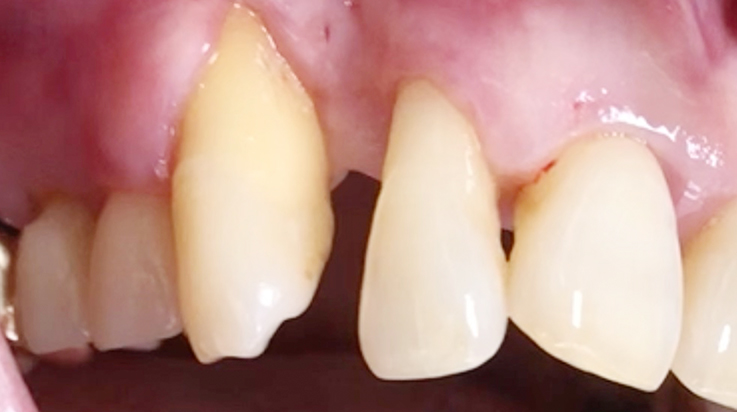

A surgical procedure using resorbable membrane

• A surgical procedure using resorbable membrane 2